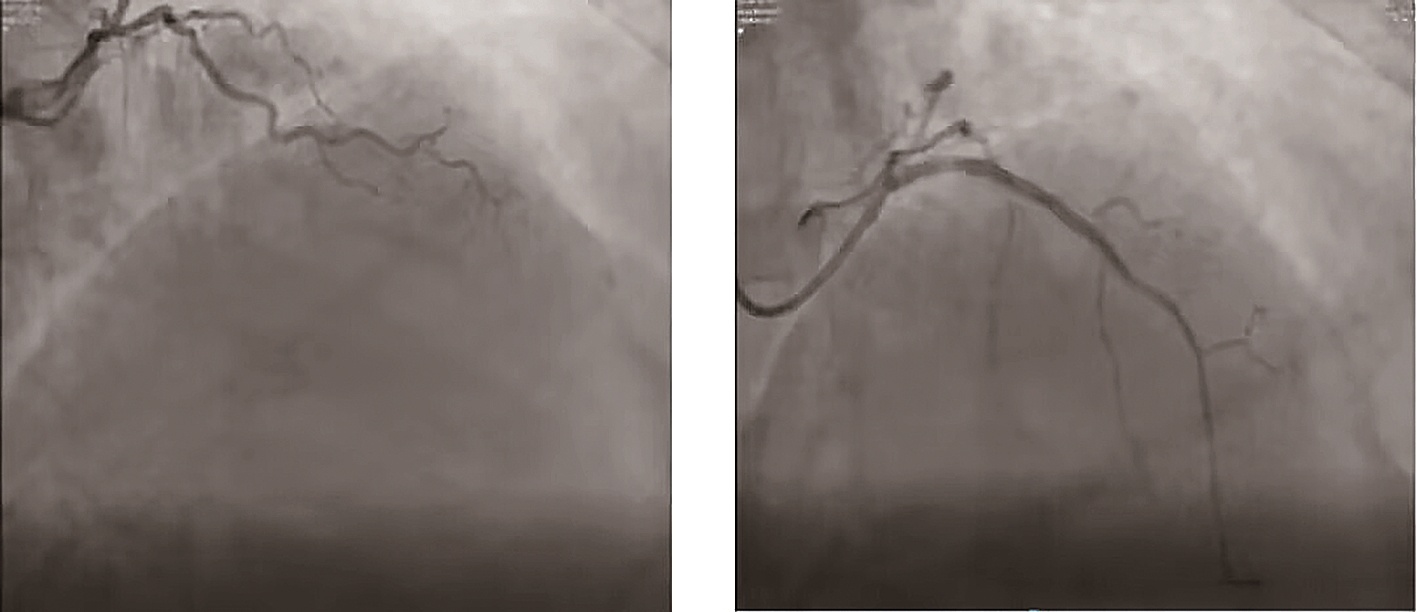

冠脉造影下术前术后对比 通讯员供图

很快,刘亮团队为刘爹爹实施冠状动脉造影术,术中提示,刘爹爹左冠状动脉主干短,前降支开口至近段完全闭塞并严重钙化;回旋支中段动脉粥样硬化,狭窄约20%-30%;右冠中段动脉粥样硬化,狭窄约40%-50%。“左前降支是心脏血管中功能最强大的血管,而刘爹爹的这个血管近段已经完全闭塞,病情严重程度可想而知。”刘亮表示,刘爹爹是冠状动脉慢性完全闭塞病变(CTO病变),病情严重需要尽快手术。

刘亮介入团队讨论认为,对刘爹爹这么严重病情的患者,最好的治疗方案就是外科开胸搭桥,但考虑到高龄及外科搭桥手术的风险,刘爹爹和家属都不愿进行外科搭桥治疗,并要求做冠脉支架植入治疗(PCI)。由于刘爹爹冠脉严重狭窄,而且闭塞段有钙化,导丝常难以顺利通过病变。刘亮团队在延长导管及微导管加强支撑下经过反复尝试,最后将XT-R导丝顺利通过闭塞段微通道,植入支架3枚,打通了刘爹爹心脏的“生命线”。